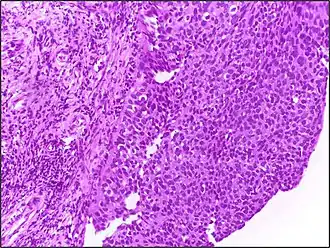

Дисплазию шейки матки часто называют цервикальной интраэпителиальной неоплазией шейки матки (CIN — Cervical Intraepithelial neoplasia). Она часто классифицируется следующими степенями, в зависимости от наличия аномальных клеток на поверхности эпителия:

- CIN 1 (дисплазия слабой степени) — характеризуется невыраженными изменениями строения эпителия с умеренной пролиферацией клеток базального слоя. Характерными признаками является наличие морфологических признаков папилломавирусной инфекции — койлоцитоз и дискератоз. Эти изменения не должны охватывать более одной трети толщины эпителиального пласта, начиная от базальной мембраны. Это создает условия для затрудненной диагностики, поскольку забор материала для цитологического исследования во время скрининговых исследований не во всех случаях может быть большим по объёму и глубине.

- CIN 2 (дисплазия средней степени) — имеет более выраженные морфологические изменения. При этом поражается половина толщины эпителиального слоя, начиная от базальной мембраны.

- CIN 3 (дисплазия тяжелой степени) характеризуется поражением более двух третей эпителиального пласта. Морфологические изменения весьма выражены. Для данной стадии характерно появление патологических митозов, а также наличие огромных гиперхромных ядер клеток.